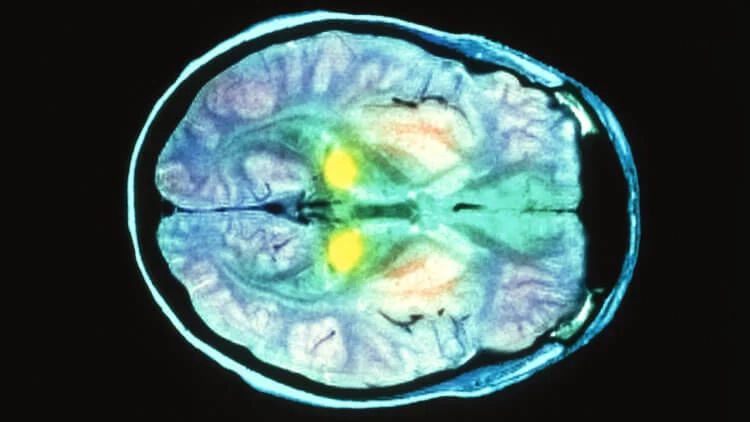

Нейродегенеративные заболевания, вызваны прионами, буквально превращают мозг в губку.

Сканирование мозга пациента с болезнью Крейтцфельдта-Якоба.